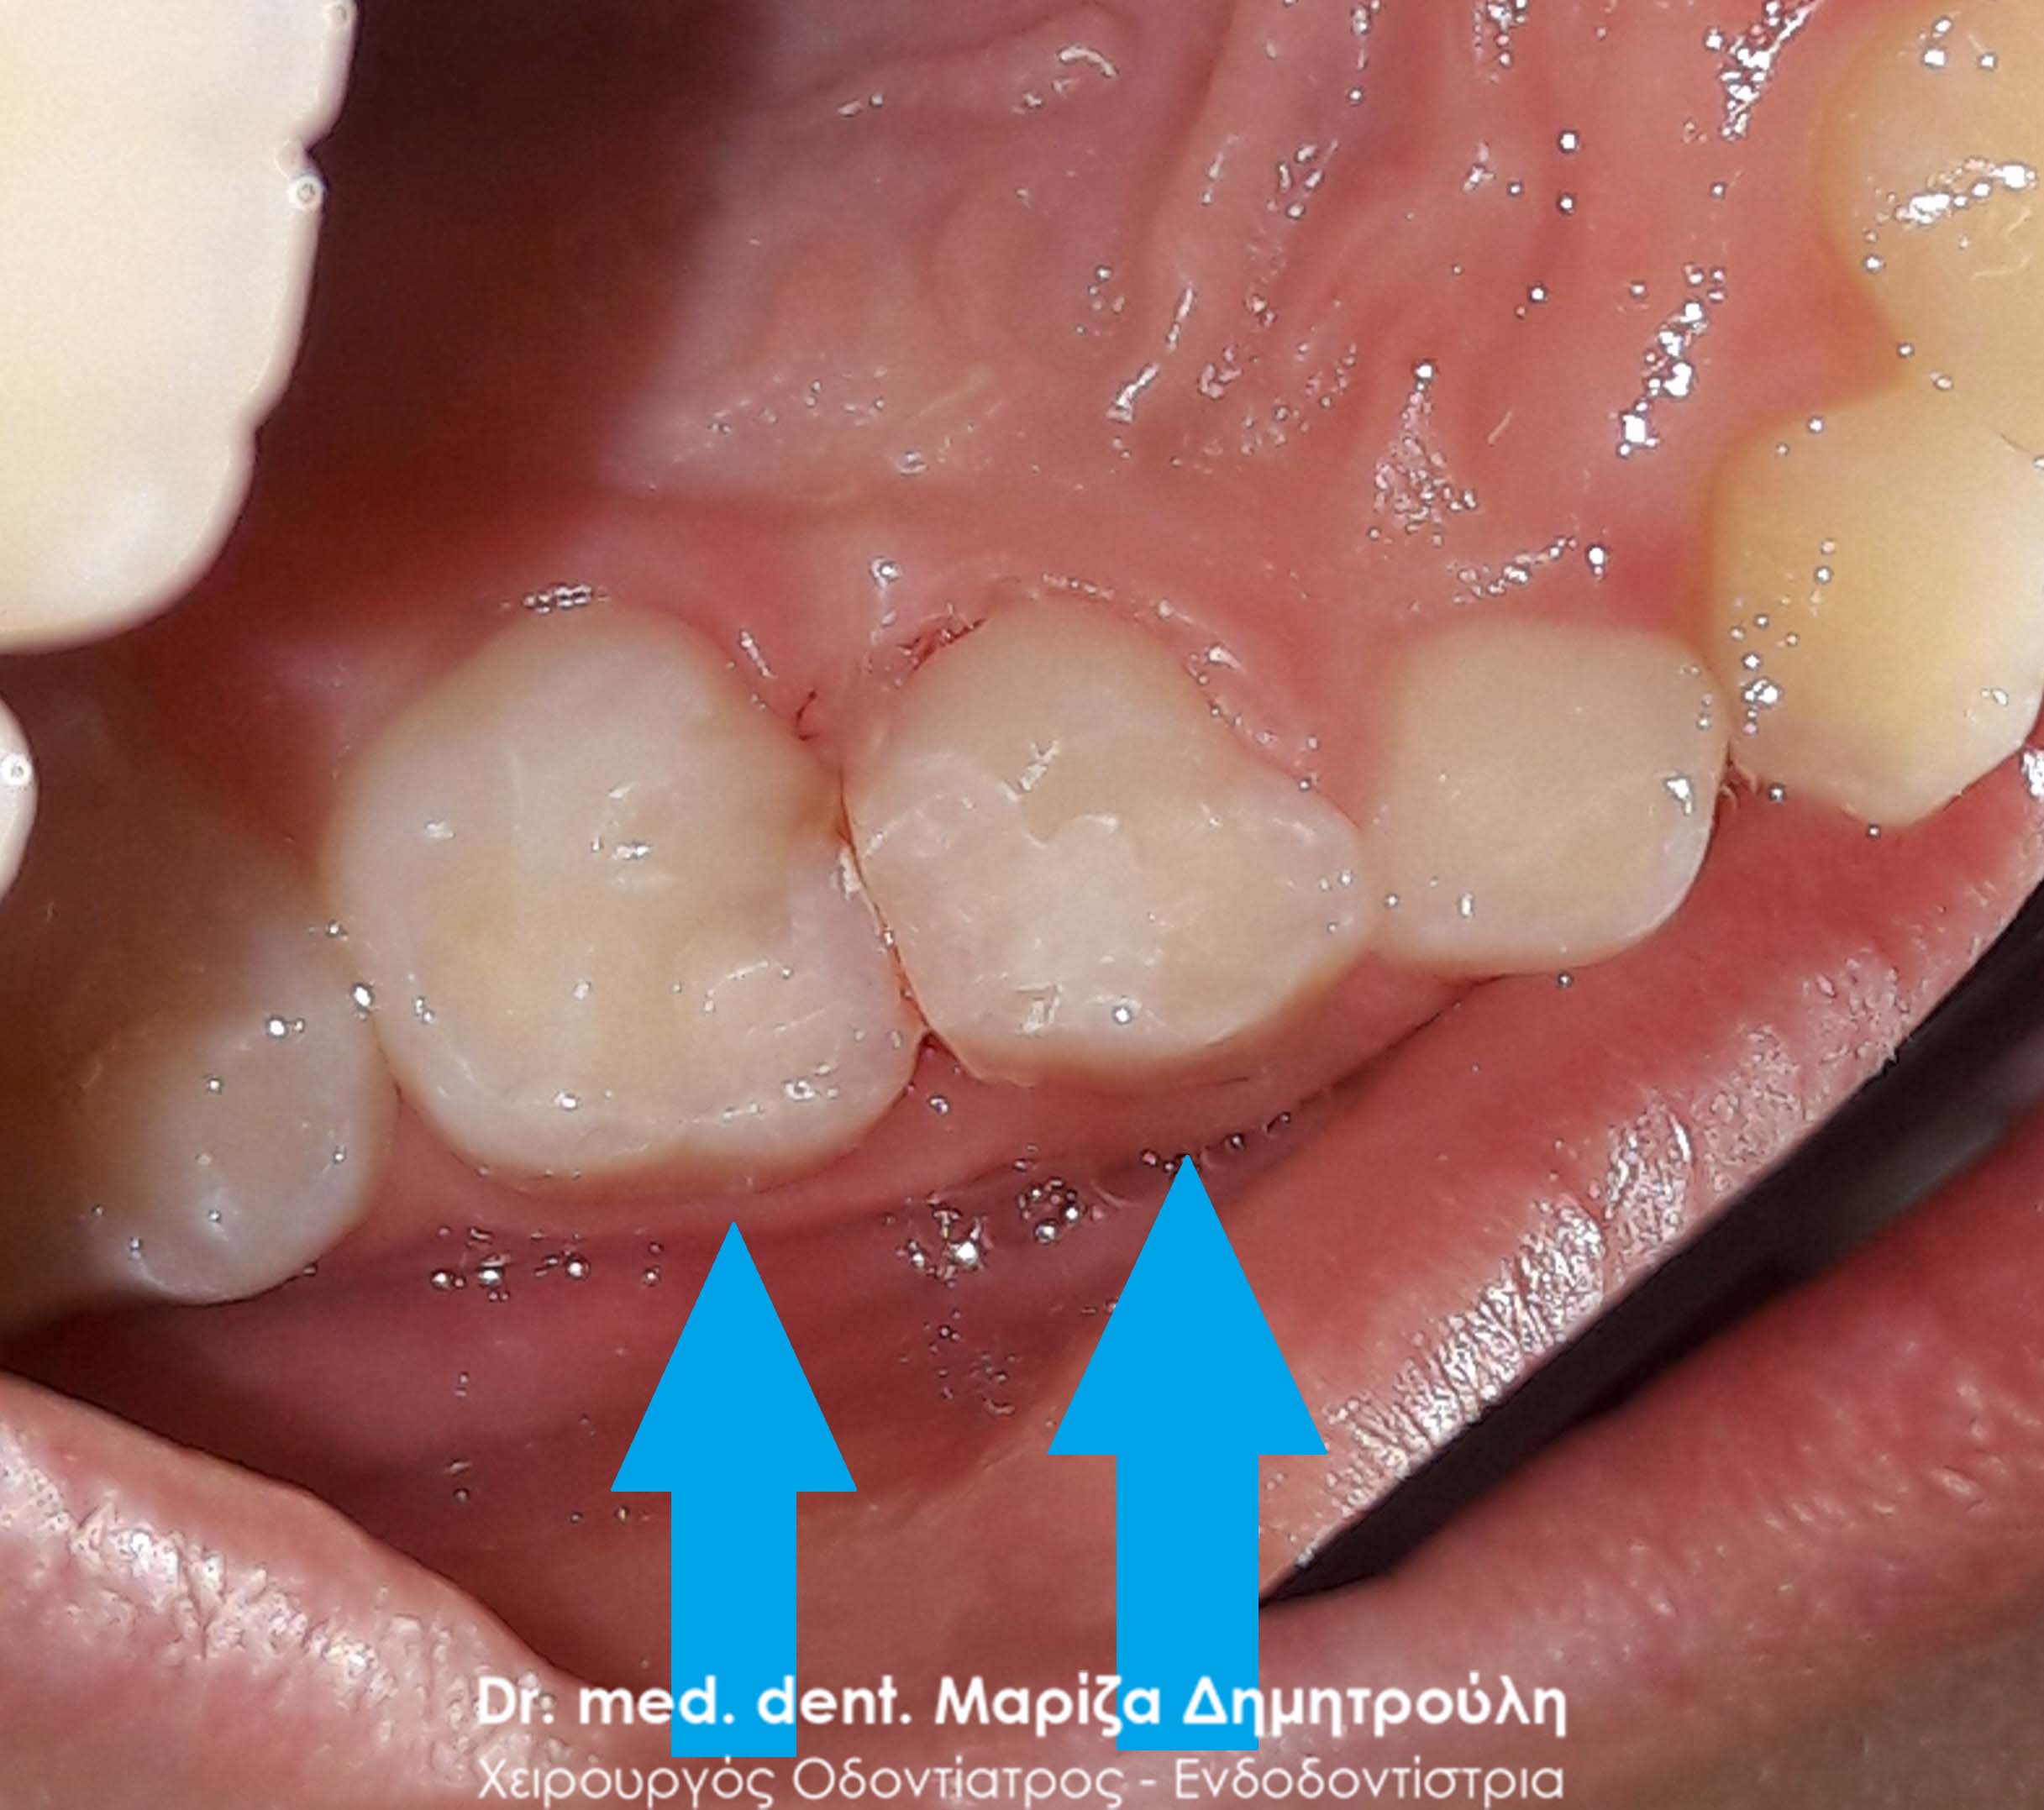

Dental filling of primary tooth

AFTER